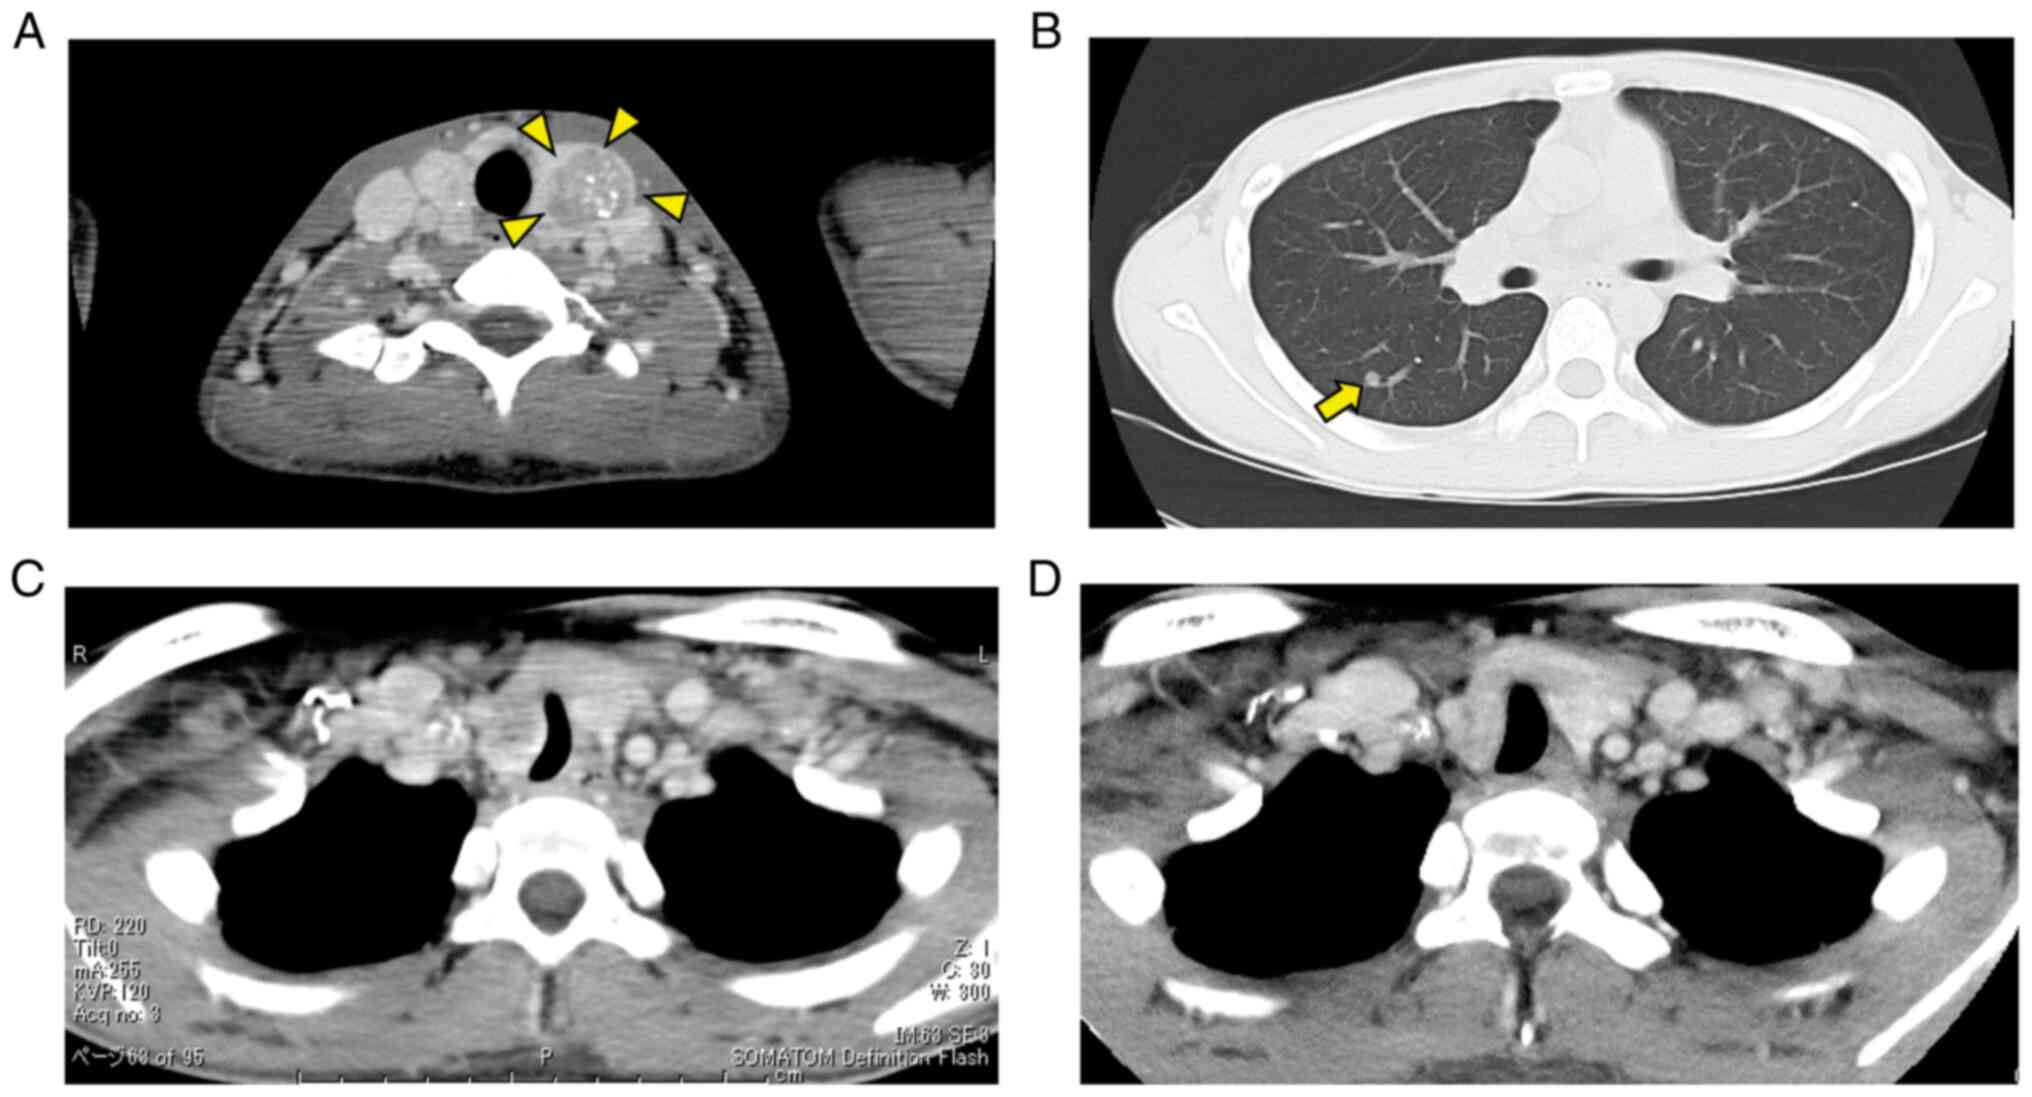

The first case was that of a 19-year-old male presenting with cervical swelling, dyspnea and chronic diarrhea. Peculiar physical features included neuromas of the tongue (Fig. 1A) and eyelid (Fig. 1B), as well as marfanoid habitus (Fig. 1C). A blood test revealed high levels of carcinoembryonic antigen (CEA) and calcitonin (Ctn). Computed tomography (CT) showed unresectable tumors of the thyroid, bilateral neck lymphadenopathy (Fig. 2A) and multiple nodules in both lungs (Fig. 2B). The trachea was narrowed and deviated due to a thyroid mass (Fig. 2C). Histologic examination confirmed a diagnosis of MTC (cT4bN1bM1, stage IV). Due to lung metastases, vandetanib, a tyrosine kinase inhibitor, was administered. The daily dose of vandetanib was 300 mg. Cardiovascular monitoring was also performed to control electrolyte disturbance-related adverse events due to persistent diarrhea and arrhythmia, such as QT prolongation. Although QT prolongation developed in the patient, the treatment continued without complication. After starting treatment with vandetanib, diarrhea persisted with varying severity. On the contrary, the tumor size was mildly reduced (Fig. 2D). All the nodules in the lungs disappeared. At 25 months after the initial treatment, the patient remains in good condition and the disease has shown no progression. Genetic testing identified the RET mutation in the M918T codon. As the patient confirmed MEN2B, the authors suggested genetic counseling for the family.

Figure 2

Computed tomography (CT) scan results of Case 1. (A) A thyroid tumor is shown (surrounded by arrowheads). (B) The CT scan demonstrates lung metastasis (pointed with an arrow). (C) The trachea was narrowed and deviated by the thyroid mass. (D) The CT scan shows an improvement in tracheal deviation in Case 1 after initiation of treatment.